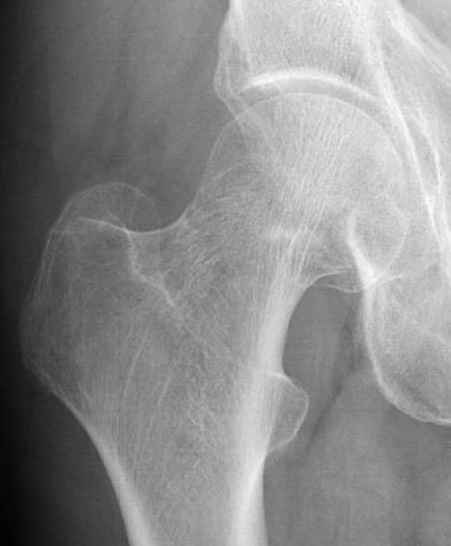

Перелом конечно не вколоченный т.к. видно линию перелома и нет суперпозиции костной ткани.

Добрый день. Перелом коварный. Через время может произойти лизис в области "неполного" перелома и он превратиться в "полный" со всеми очевидными проблемами, тем более у пациента, склонного к питию. Если не разовьется делирий или после выхода из него, рекомендую внутренний остеосинтез винтами.

Профилактику дальнейшего раскола неполного перелома шейки провели тремя канюлированными шурупами.

Выбор методики фиксации зависит от качества кости и смещения перелома. Желательно фиксацию проводить минимальным и жестким методом, для перелома без смещения и без остеопении перкутанные шурупы - идеальный метод.

И вне контекста, еще...по классификации Devas cтрессовые переломы шейки разделяются на тензионные и компрессионные. У молодых обычно происходит по типу компрессионных переломов, они более стабильные, а у пожилых по типу тензионных (дистракционных) переломов.

Молодым дисциплинированным больным можно рекомендовать щадящее консервативное лечение на костылях. Критерием являются несмещенные переломы с обязательным частыми рентгенгенологическими наблюдениями. (См. приложенный алгоритм)

Снимок сустава с внутренней ротацией покажет абнормальную шейку, хотя золотым стандартом является Магнитно-резонансая томография.